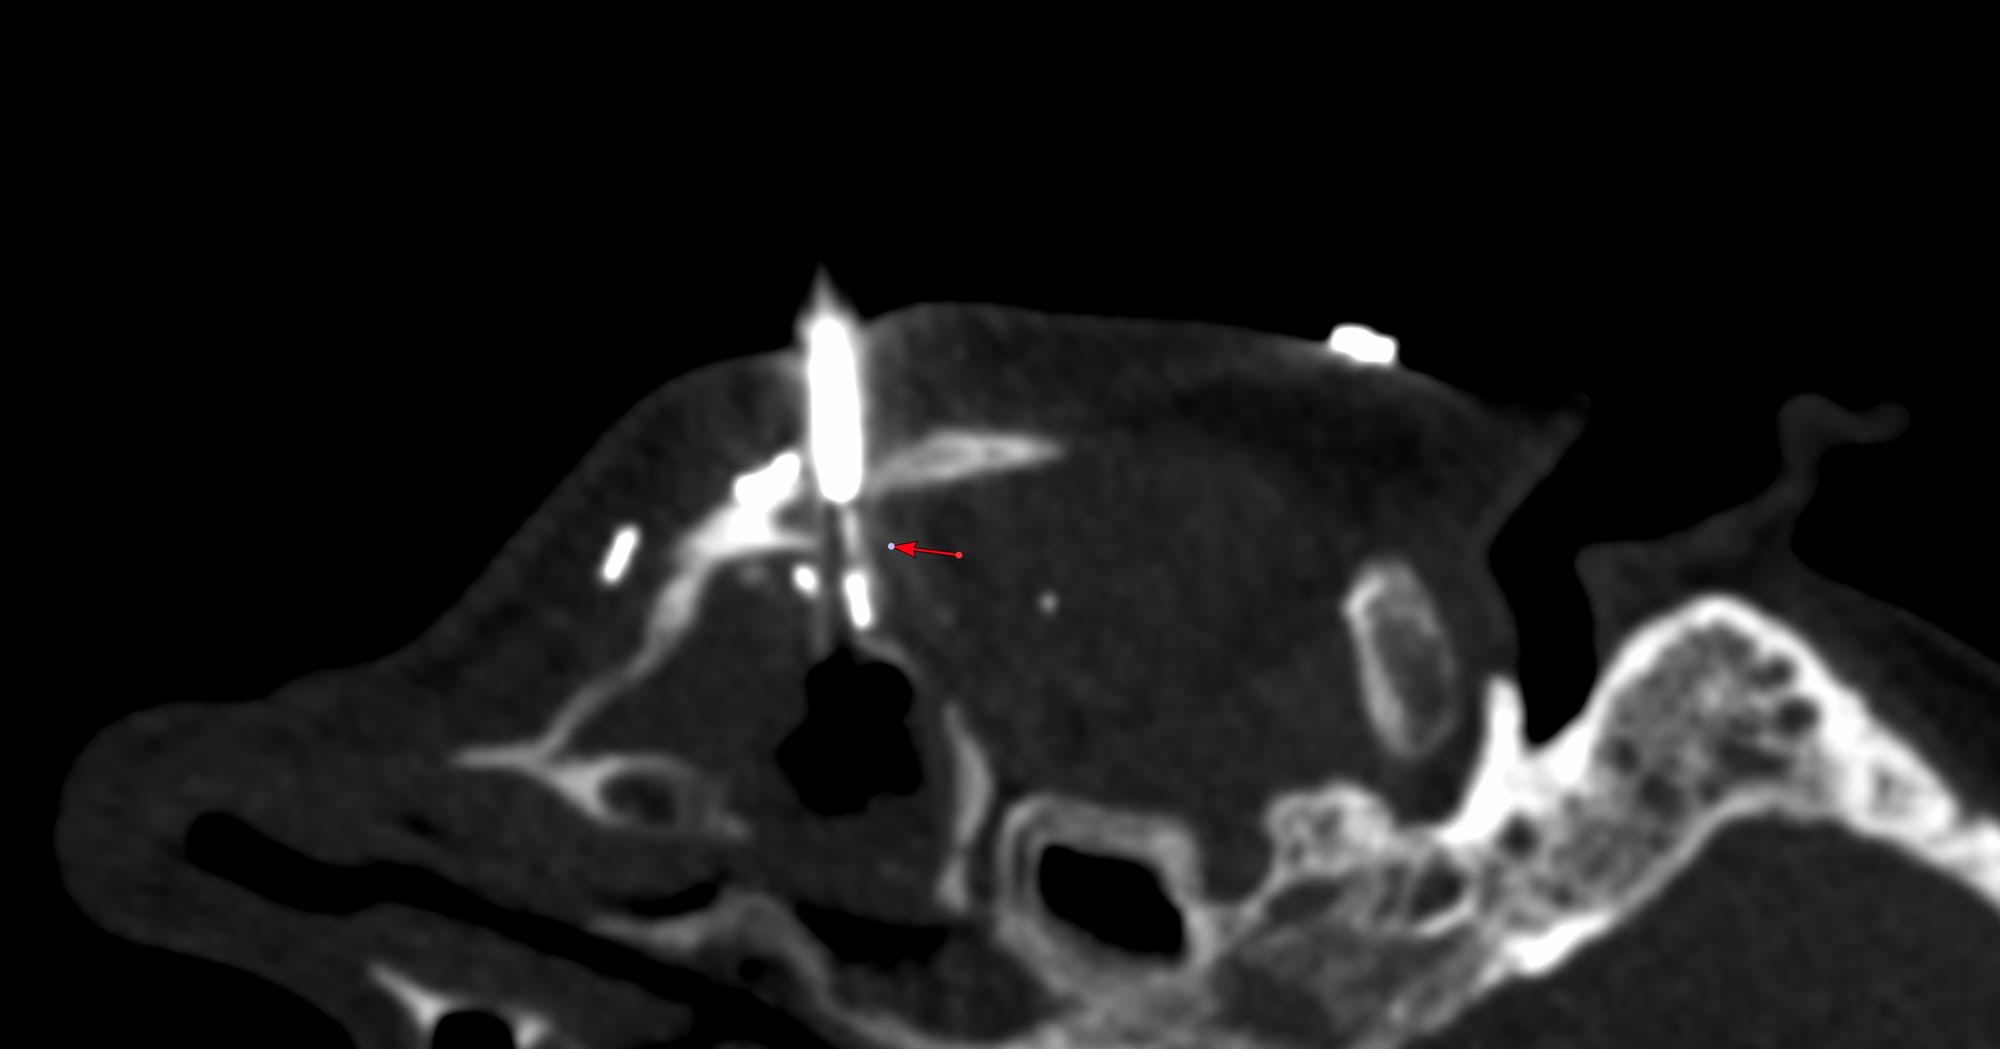

COD 127 - Maxillary Sinus Biopsy

Bhavin Jankharia - 09 November 2025